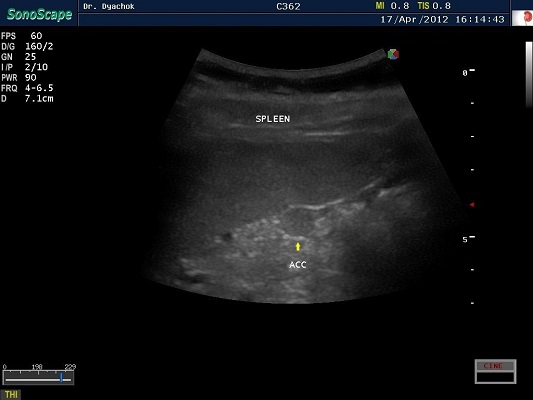

SonoScape S2N Vet – уникальная узи-система, выполненная в виде портативного ноутбука для легкой переноски. Отличается эта система цветным форматом визуализации, а также крайне чувствительными доплеровскими режимами, работающими на уровне премиальных аппаратов. При оптимальной цене – это очень хорошее и сбалансированное решение для ветеринарной клиники.

Диагональ монитора составляет 15,6 дюймов, что обеспечит комфортную работу для врачей и полный спектр визуализации для пациентов. Компактный вес не превышает 5 кг. (вместе с батареей), что оценят выездные бригады скорой помощи или ветеринары, выезжающие на дом.

Цифровая рабочая станция S2N Vet предполагает наличие жесткого диска для записи данных, составление и экспорт отчетов с возможностью добавления изображений, ведение базы данных пациентов.

Режимы сканирования SonoScape S2N Vet:

• В, М, В/М, В/В, 4В, Тканевая гармоника;

• Изменение масштаба изображения в режимах реального времени и стоп-кадра;

• Цветной, энергетический, направленный энергетический, импульсно-волновой,

• Постоянно-волновой допплер;

• Дуплексный, триплексный режимы;

• Трапецеидальное сканирование на линейных датчиках;

• Режим панорамного сканирования;

• Технология подавления спекл-шума MicroScan.